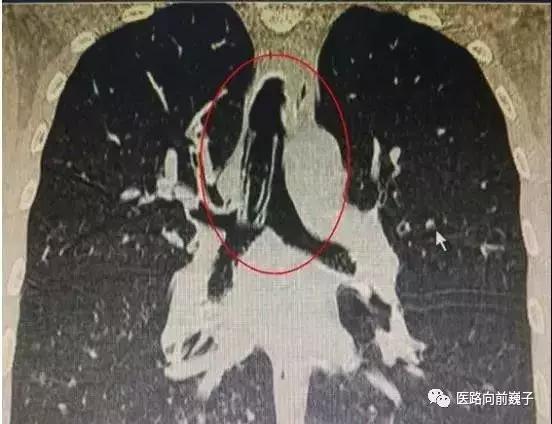

图片与内容无关